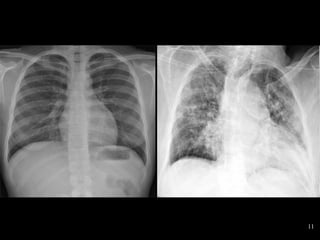

Consolidated lungConsolidated lung